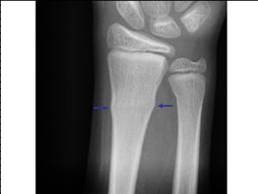

Avulsion fracture

A fracture in which a fragment of bone has been pulled away by a tendon and its attachment. Common in children